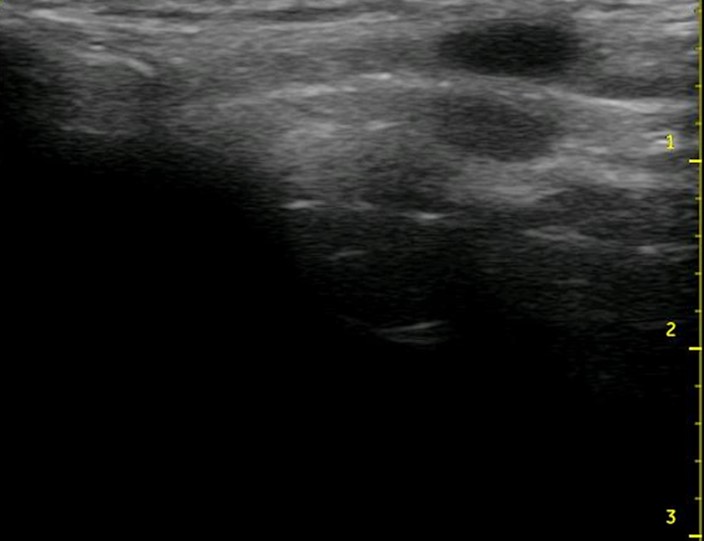

Figure 3. A porcine model for teaching ultrasound-guided cricothyrotomy